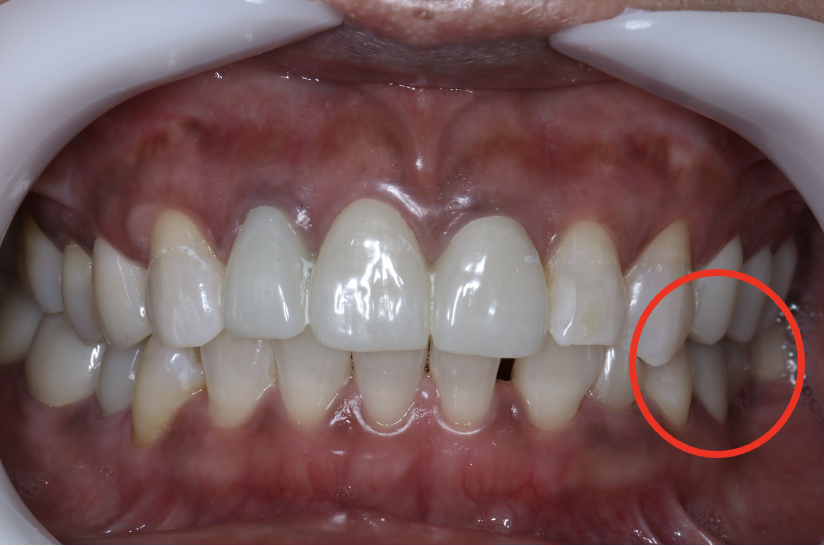

インプラント症例④

年齢 50代女性

治療期間 4ヶ月

インプラントメーカ ジンマーインプラント

治療内容 カスタムアバットメント、上部ジルコニア

治療箇所 左下6番

治療費用 380,000円